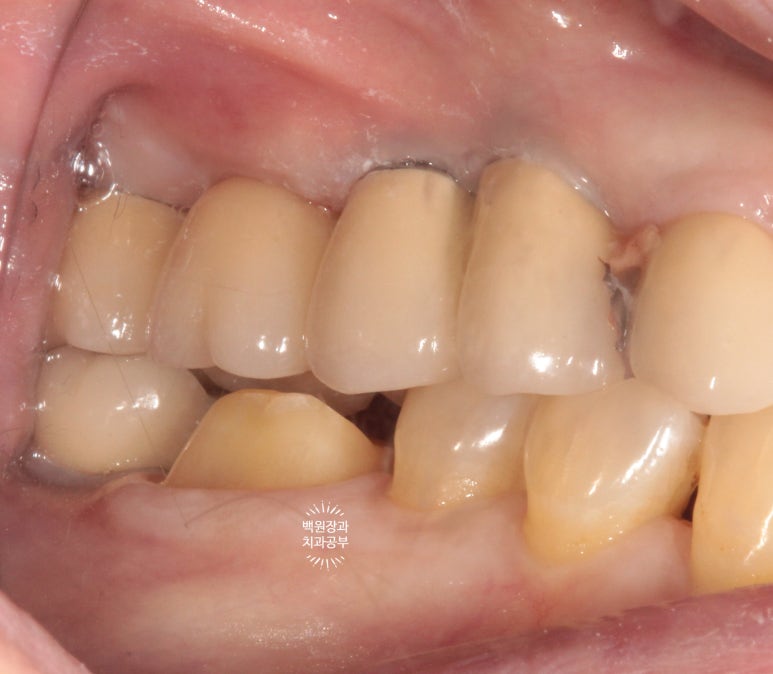

옆에서 보았을 때도 모양이 깔끔합니다.

당연한 과정이지만, 교합이 형성되도록 물었을 때 제작될 크라운의 두께가 충분한지도 반드시 확인해야합니다.

너무 얇은 지르코니아 크라운을 붙여드리면 금방 깨질 수 있으니깐요.

보시면 뒤에 위치한 임플란트의 치아 (구멍 있는 치아)와 앞에 위치한 작은 어금니와 넓은 접촉면을 형성하고 있는 것을 보실 수 있을거에요!

보철물은 치아에 비해 불완전하여 음식물이 쉽게 낍니다. 최대한 넓은 면적으로 접촉면을 형성해주는게 중요해요.